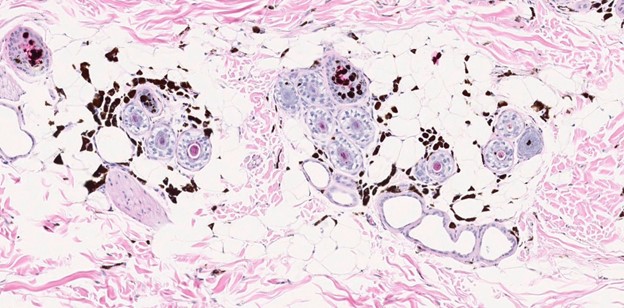

Figure 6. H&E, 10x magnification |

|